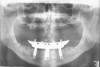

Dental technicians played a magnanimous role in the creation of early fixed implant prostheses. They began working with impression copings and gold cylinders to wax their frameworks prior to casting.10 Synergy between doctor and technician was critical to effect a successful casting "try-in" visit with the patient that could progress to the final stages of processed acrylic-on-metal prostheses. In a recent informal ergonomic study, the author (TJB) determined that the hands-on time needed by a certified dental technician to complete a screw-retained implant-supported prosthesis circa 1985 (Figure 1 and Figure 2) was 18 hours. Ensuring excellence in function and esthetics at that time in implant history required rigidly sequential steps, a high level of skilled judgment, well-tuned collaboration with the laboratory, and a significant investment in time. Fixed implant prostheses emerged as a treatment of choice but were costly to produce and, therefore, expensive for patients. Treatment acceptance was restricted.

Fig 1. Cast hybrid framework utilizing high noble alloy, circa 1985; buccal view (Fig 1) and occlusal view (Fig 2).

Figure 1

Fig 2. Cast hybrid framework utilizing high noble alloy, circa 1985; buccal view (Fig 1) and occlusal view (Fig 2).

Figure 2